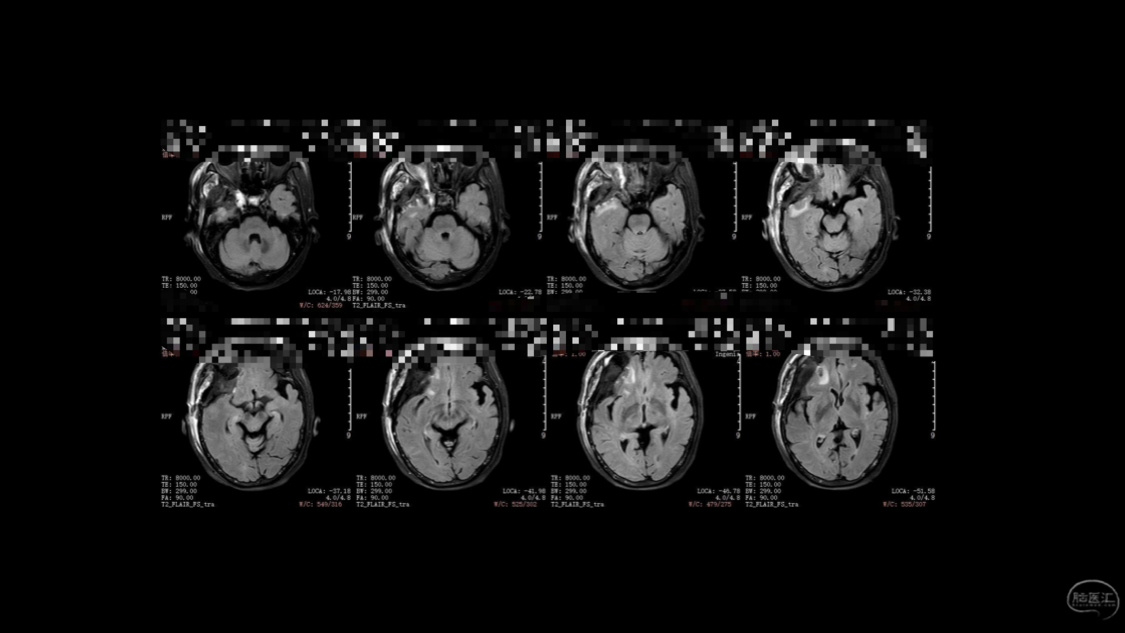

陈保东教授手术作品-右眶内及海绵窦旁孤立性纤维瘤